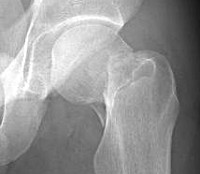

Перелом шейки бедра у пожилых людей. Распространенная тяжелая травма, которая может стать причиной возникновения целого ряда опасных осложнений, обострения различных заболеваний и даже летального исхода. Причиной повреждения обычно является незначительная травма, возникшая на фоне остеопороза и других заболеваний, сопровождающихся снижением прочности костей. Проявляется умеренной болью, ограничением опоры и движений. Для подтверждения диагноза используют рентгенографию. Переломы шейки бедра самостоятельно не срастаются, поэтому при таких травмах показано хирургическое лечение. Если операция невозможна из-за общего состояния пациента, проводят паллиативную терапию.

Перелом шейки бедра - травма, возникающая преимущественно в пожилом и старческом возрасте. Отличительной особенностью данного повреждения является отсутствие сращения, обусловленное недостаточным кровоснабжением шейки и головки бедра, и высокая вероятность развития различных осложнений, связанных с вынужденной неподвижностью пожилого пациента, нередко страдающего тяжелыми соматическими заболеваниями. Перелом шейки бедра обычно выявляется у людей старше 65 лет, при этом женщины страдают в четыре раза чаще мужчин, что обусловлено более высокой склонностью к развитию остеопороза в постменопаузе.